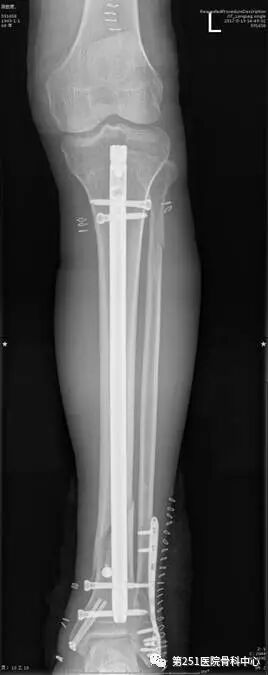

病例4:女性,车祸伤,同侧股骨、股骨颈合并胫腓骨骨折。

![]()